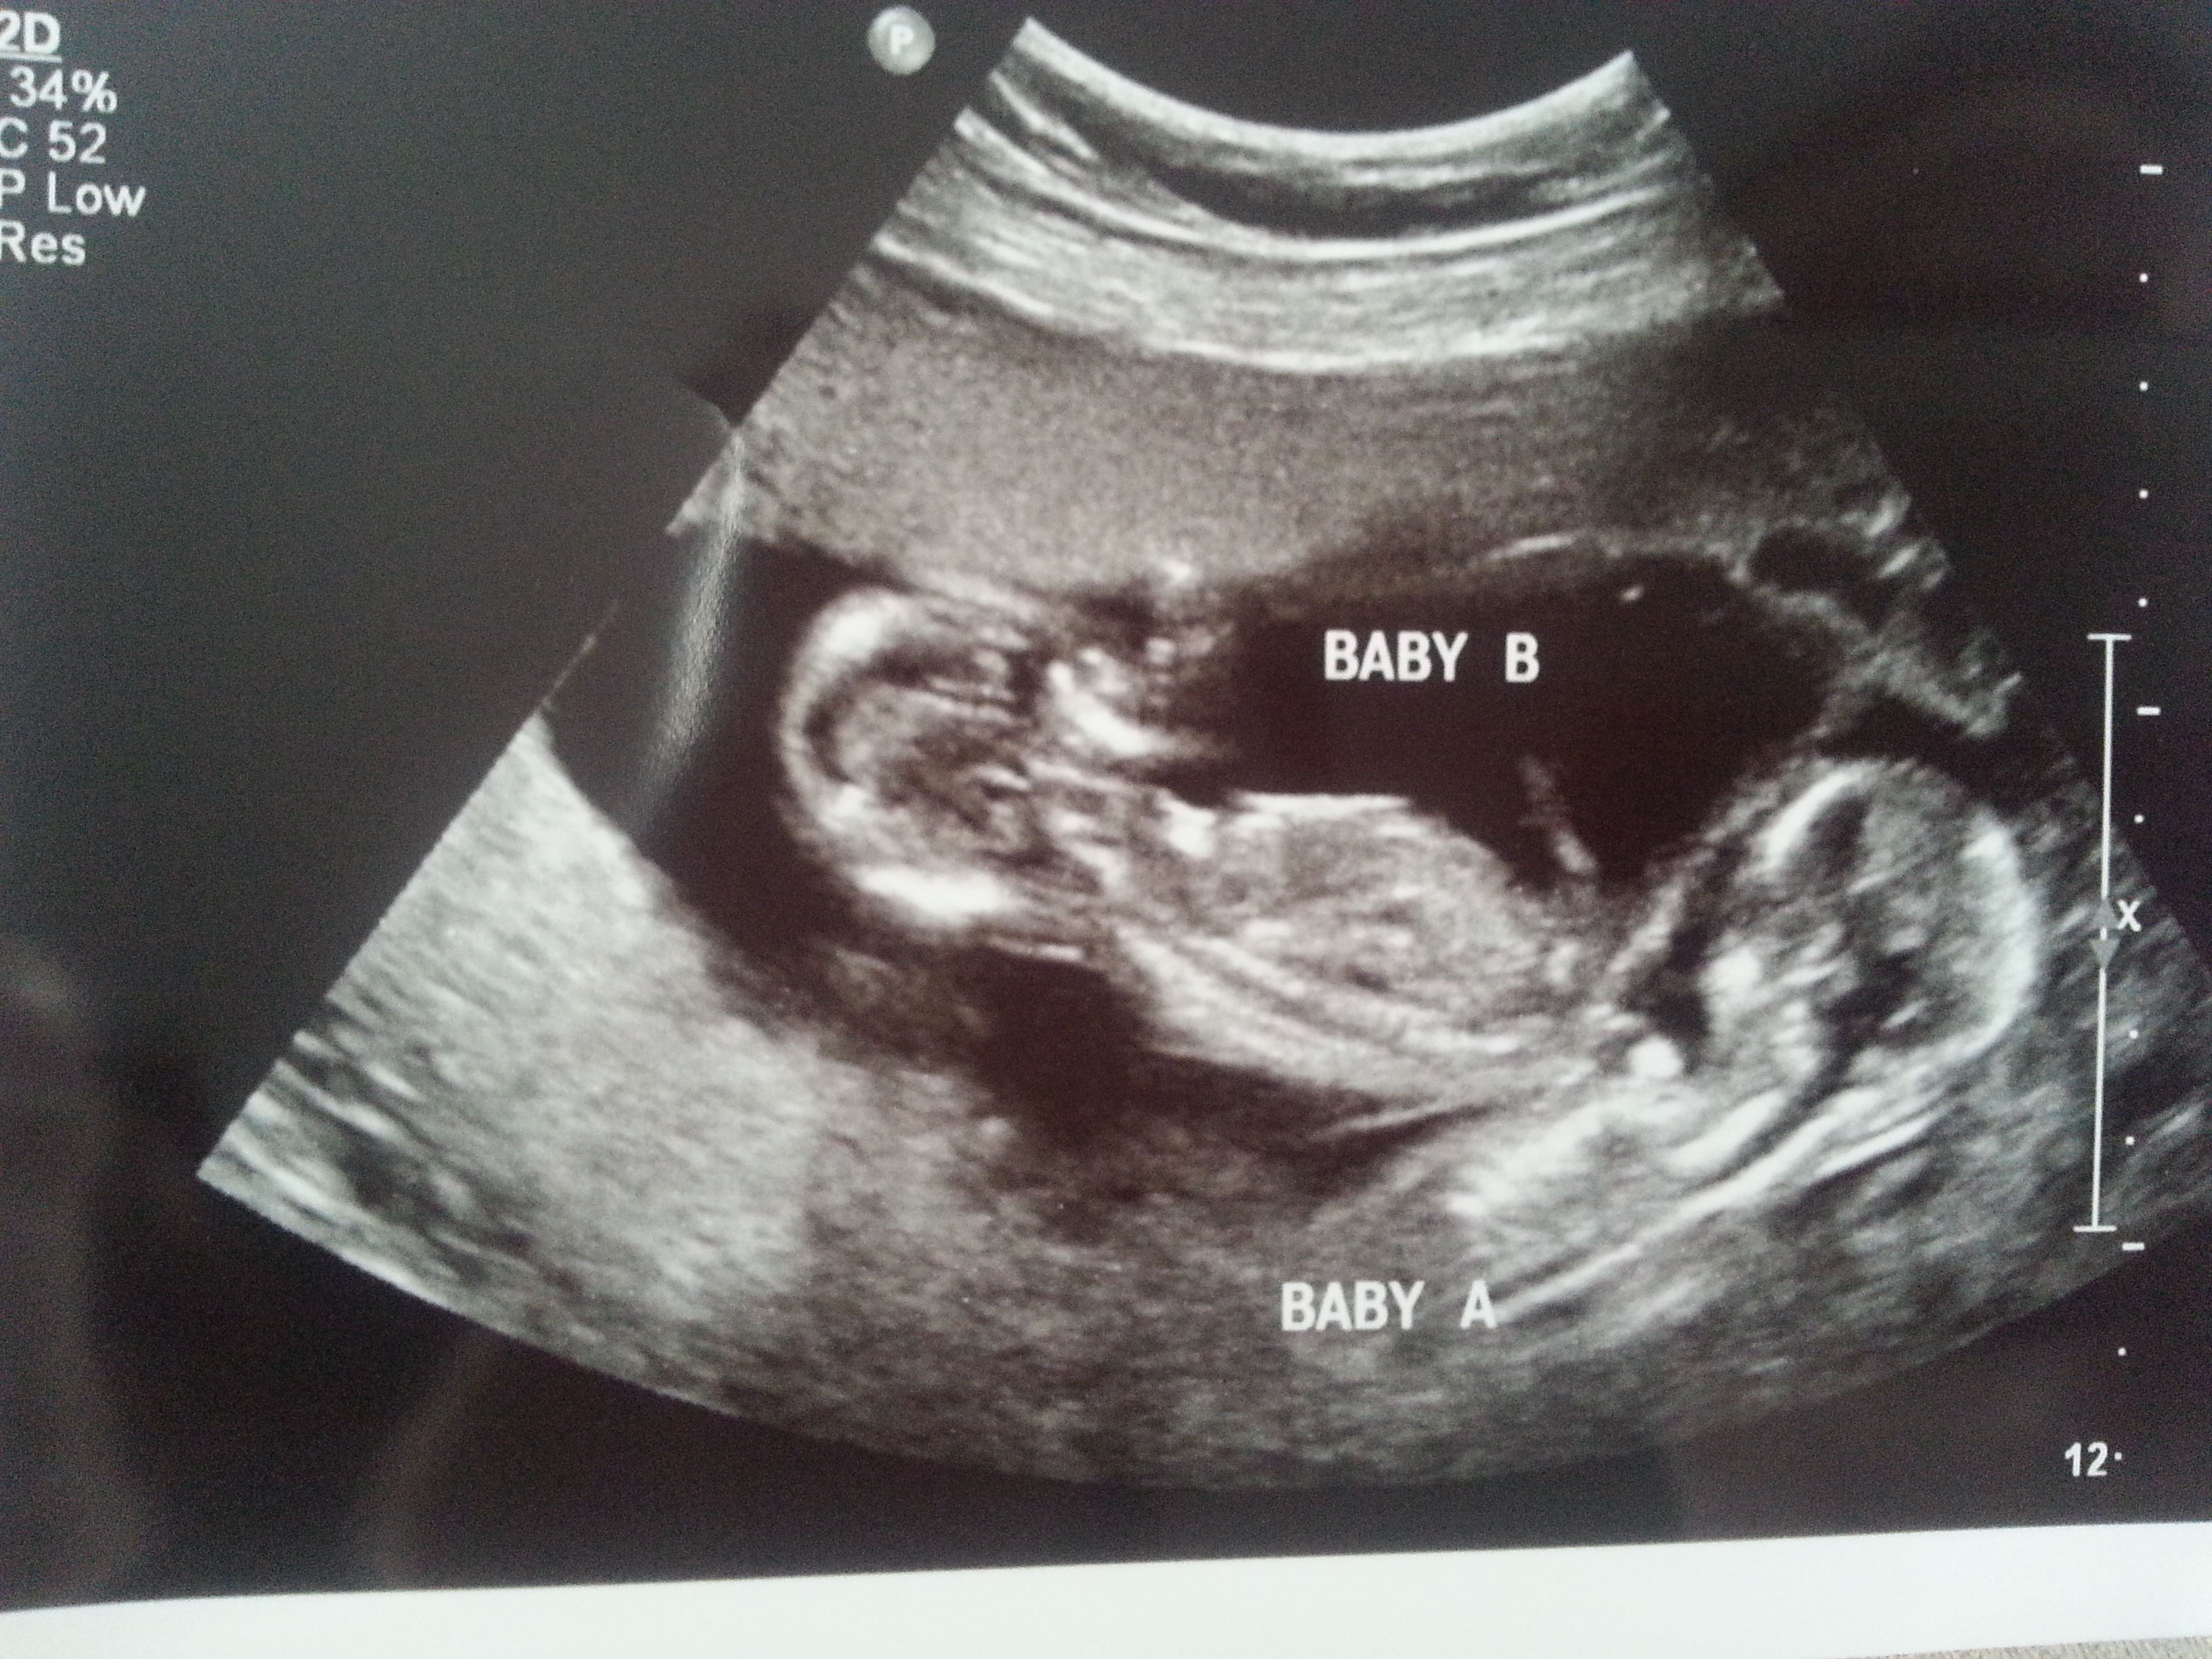

I was 12weeks 6 days and measuring 13weeks 3 days.

Attachment 23433

Attachment 23434

Maybe boy/girl. Not the best shots though!

In thinking boy/girl too.

I think B is a boy and A is a girl.

I think I'm seeing a very boyish nub for baby B. Baby A not as sure. I hope that's your girl! Congrats and good luck!

On your second pic of baby B I'm looking at the little line between the legs that's almost sticking straight up.... very boyish "angle of the dangle".

boy girl

Yip I stand by my Girl twin A and Boy lean twin B X